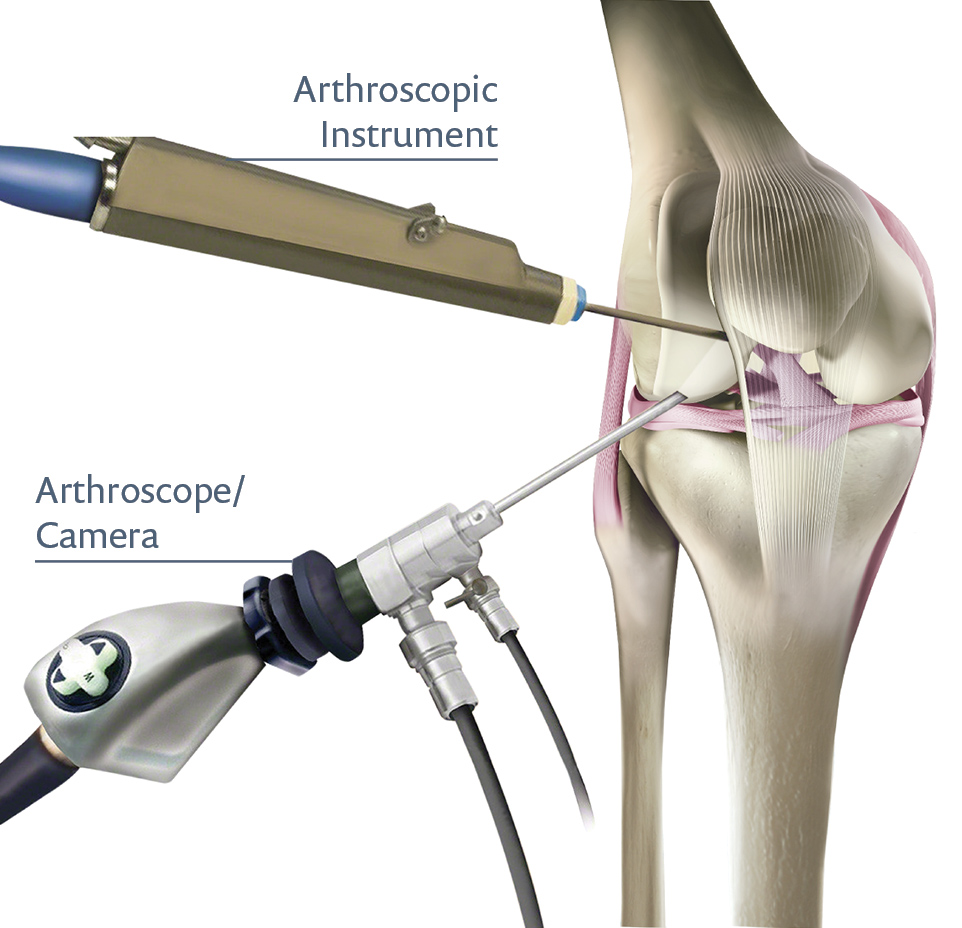

Expertise in joint replacement, arthroscopy, spine care, fractures, trauma, sports injuries, and more — offering personalized treatment to restore mobility and improve quality of life.